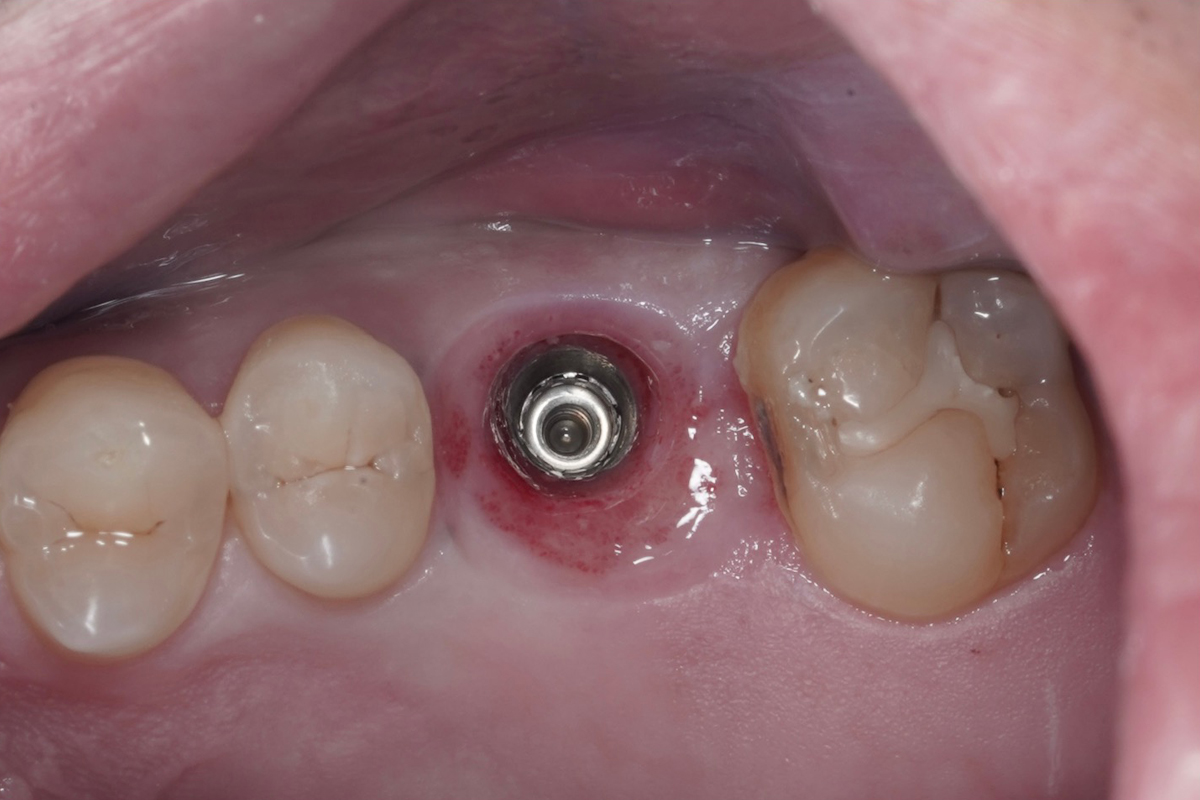

・臼歯部(奥歯)症例 [抜歯即時埋入]

AFTER

抜歯即時埋入は術後に腫れ、内出血、痛みを伴うことが多い骨造成、歯肉移植を回避することができ、治療期間も短縮される治療方法です。通常、歯を抜いてから5〜6ヶ月待ってからインプラント治療を行いますが、抜歯即時埋入は5〜6ヶ月で治療は終わります。

これからはメインテナンスのフェーズに入ります。定期的なクリーニングと咬合チェックを怠らないことで、インプラント周囲炎の発症リスクを大幅に抑えられます。